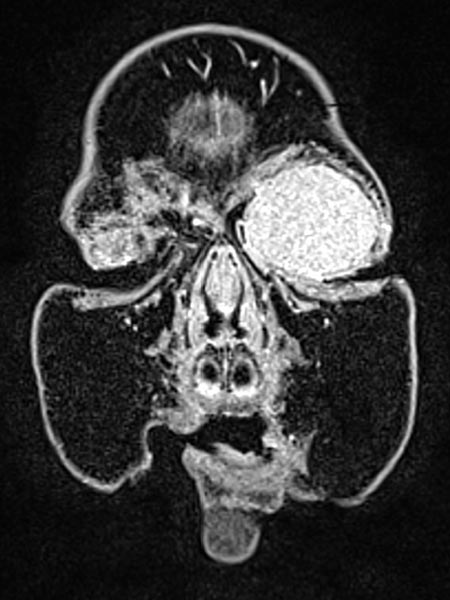

T1-weighted, coronal MRI after contrast depicts a homogeneous, strong enhancement in a solid, sharply demarcated tumor of the left eye. This is suggestive of an infantile hemangioma as part of the spectrum of vascular tumors.

T1-weighted coronal plane MRI after contrast administration in a slightly more dorsal plane shows extension of the contrast-enhancing solid mass well into the medial orbit of the left eye with displacement of the eyeball caudally and laterally.